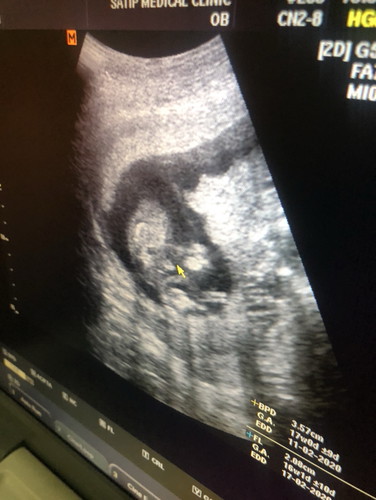

อยากรู้เพศลูกคะ

ภาพแบบนี้แม่ๆท่านอื่นพอจะดูเพศลูกออกไหมคะหญิงหรือชาย???

ชายหรือเปล่าคะดูไม่ค่อยชัดเลย คุณหมอได้บอกหรือเปล่าคะว่าญ/ช